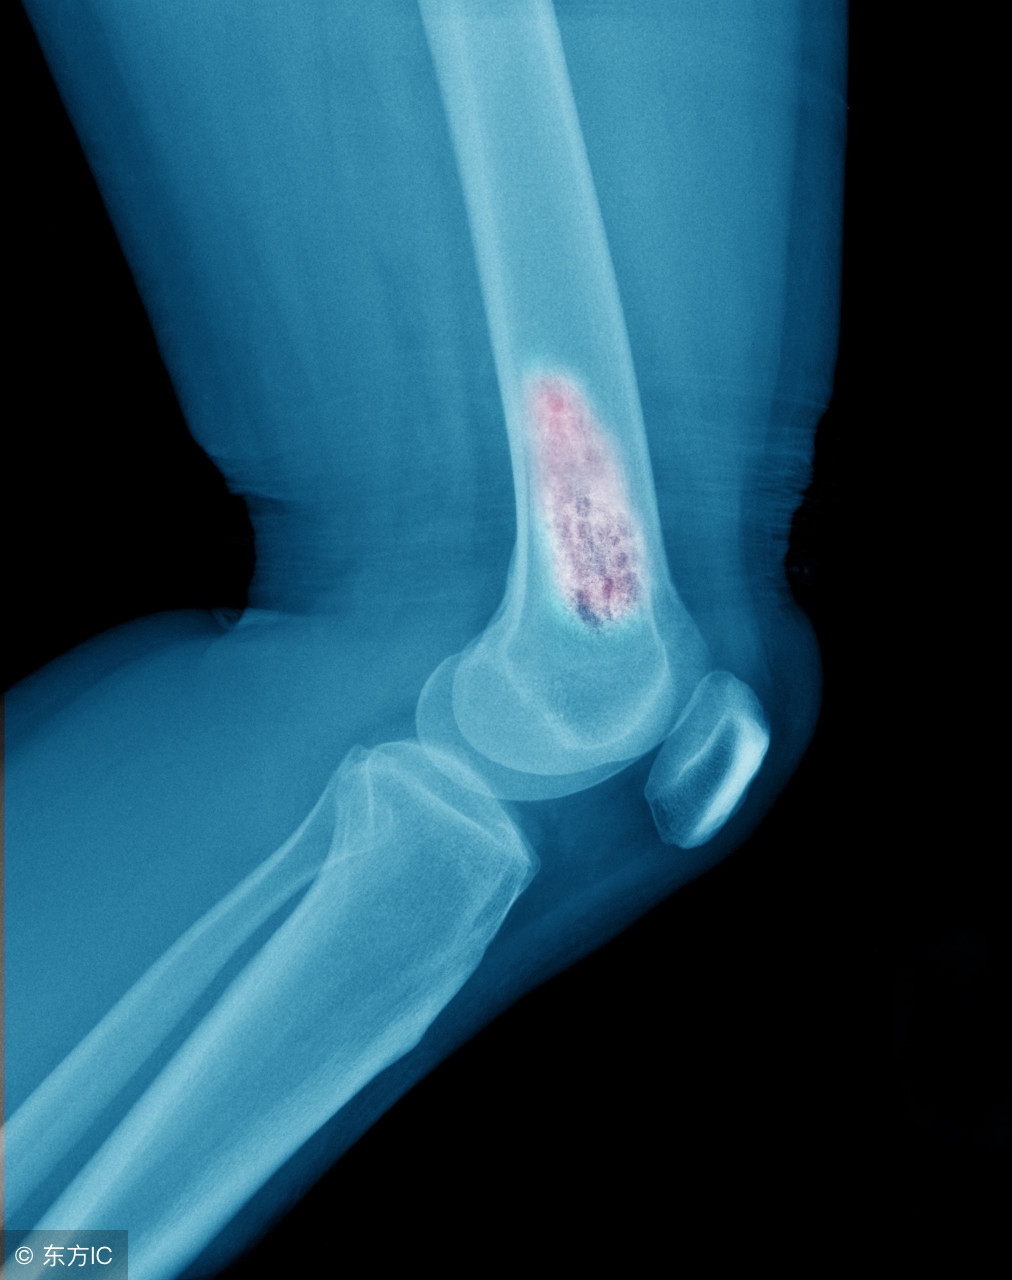

骨巨细胞瘤其实算是一种交界性的骨肿瘤,就是处于良性与恶性之间,好发于30岁左右的女性,发病率比较低,在亚洲人群发病率高于美国,约占所有原发性骨肿瘤的20%!

虽然临床上骨巨细胞瘤被当做良性肿瘤来看待,但其可以表现出恶性肿瘤样的局部侵袭性,手术后往往会有复发的倾向。另外有2%-3%的病例可能出现肿瘤的转移,最常见的是肺转移!

骨巨细胞瘤的分期

目前采用Campanacci分级系统来分级,具体如下:

I级:单纯骨头内的病变,肿瘤边界清楚,骨皮质完整;

II级:比I级更为广泛的骨头内病变,骨皮质薄,但连续性仍存在;

III级:病变突破骨头,侵犯周围软组织或者其他骨头。